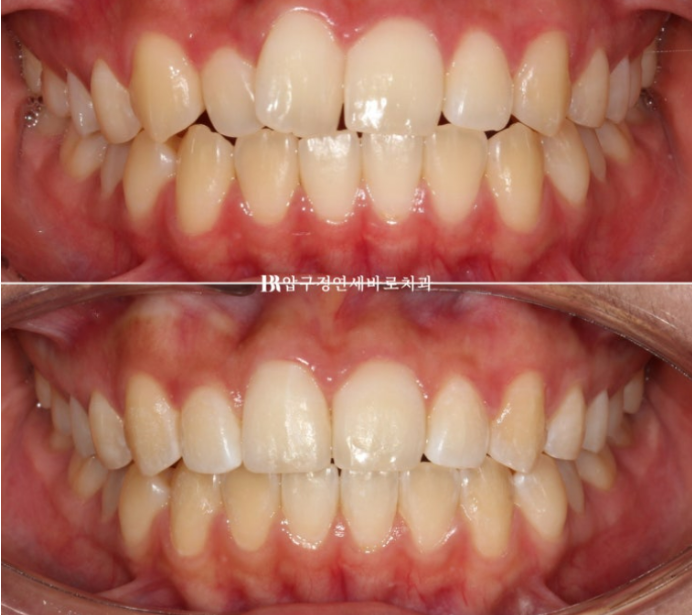

전 후 비교 보겠습니다.

토탈 치료기간은 6개월입니다.

23.12~24.06

심해보이는 덧니도 적절하게 치료한다면 의외로 짧고 간단하게 교정이 마무리가 됩니다.